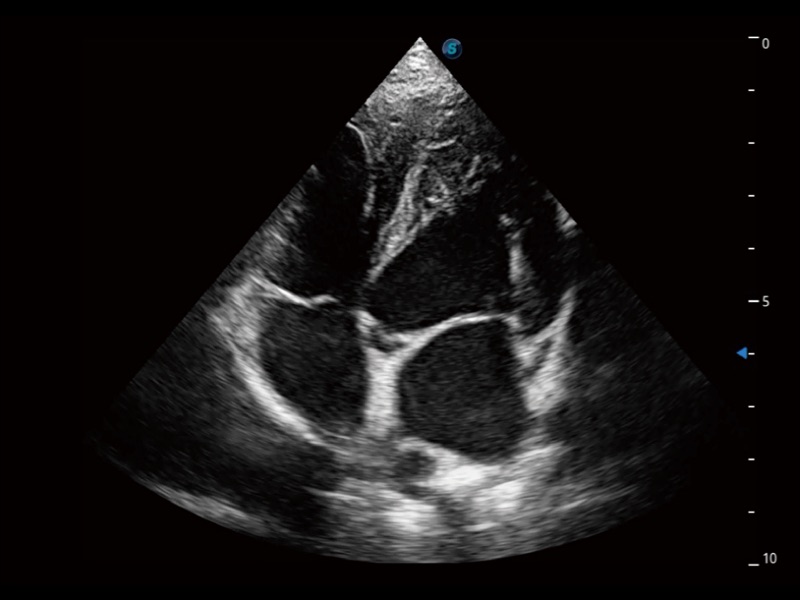

通過360度任意調(diào)節(jié)3條M型取樣線,在同一心動(dòng)周期上觀察心臟不同位置的運(yùn)動(dòng)曲線,得到準(zhǔn)確的心功能測量數(shù)據(jù),有效評估心肌運(yùn)動(dòng)及左心室功能。